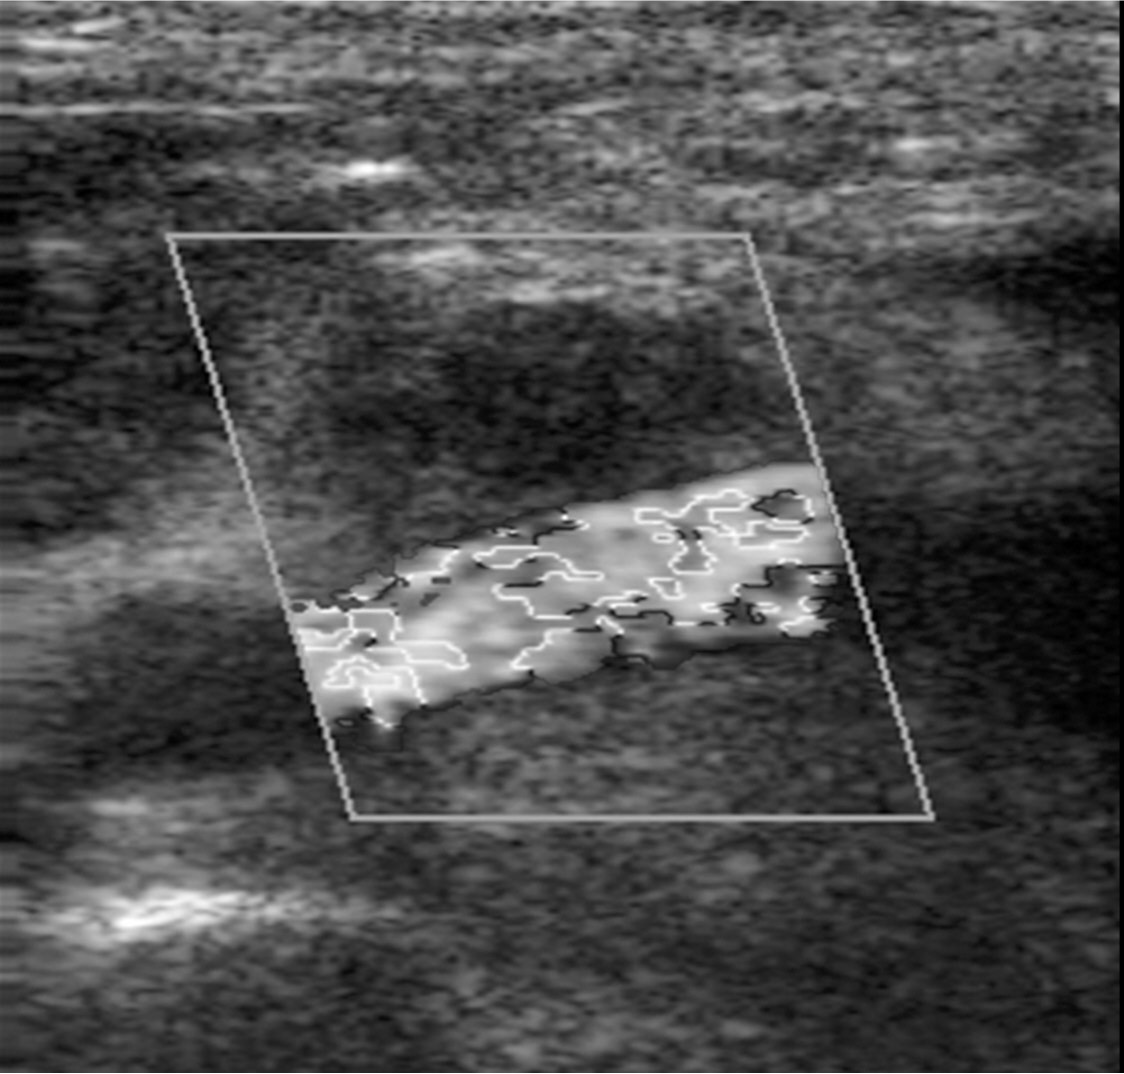

Fig. 2.

Fig. 2. Doppler US 2 days after CT scans shows enlargement in the size of the pseudoaneurysm(arrow), communicating with the right superficial femoral artery.